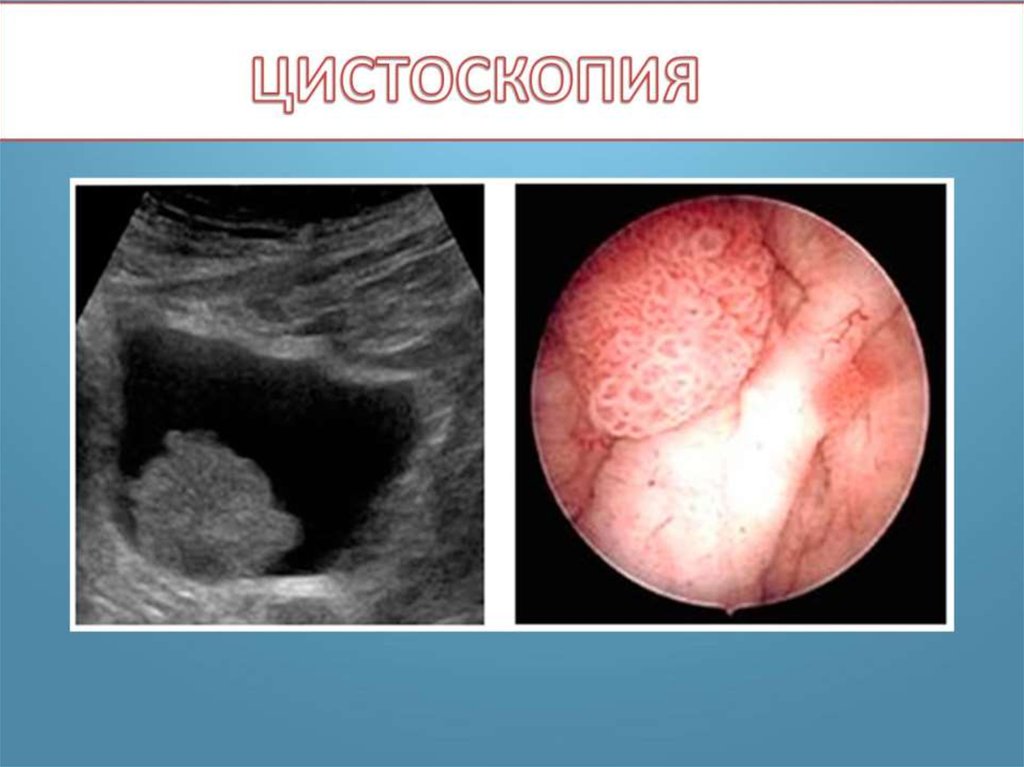

Рак мочевого пузыря